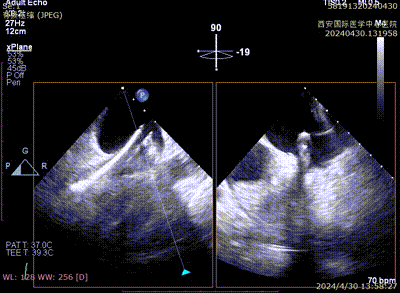

二尖瓣夹系统瓣上调整

二尖瓣夹系统进入左室

二尖瓣夹捕获瓣叶

二尖瓣夹夹闭